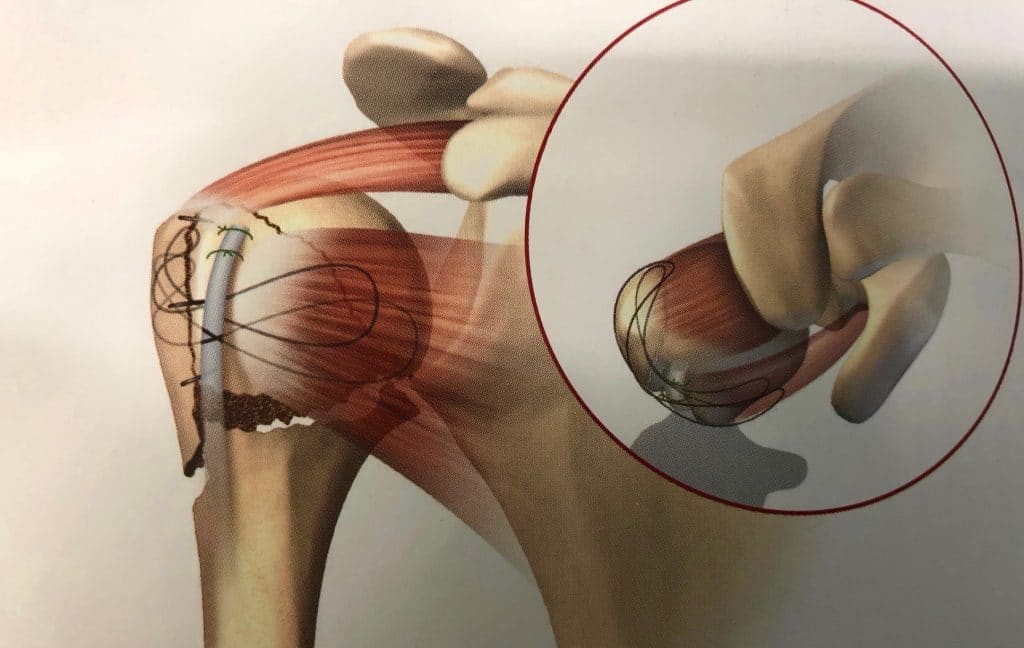

Réparation de la coiffe

L’acte chirurgical est envisagé si la rééducation ne donne pas de résultats satisfaisants. Réalisée par arthroscopie, la réparation consiste à re-fixer le tendon sur la partie supérieure de l’humérus. Cette intervention sera possible sous conditions : que le tendon ne soit pas trop rétracté, ni le muscle trop dégénéré.